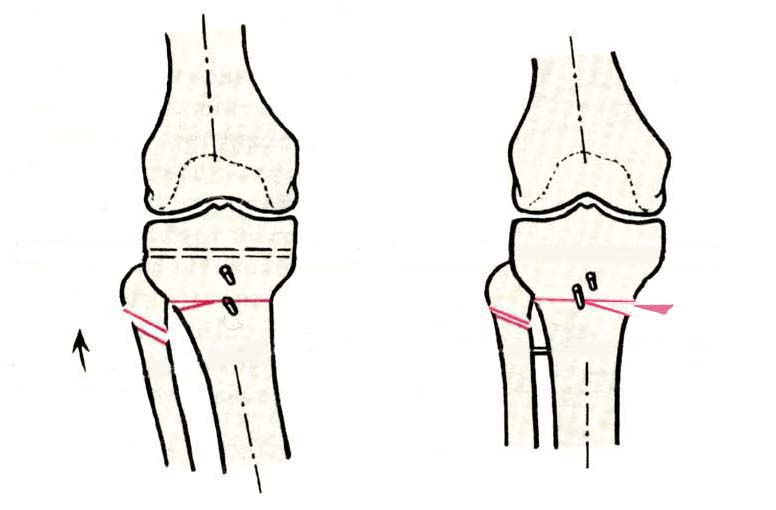

И зачем латерализация периферического фрагмента. Я всегда делаю медиализацию. См схему. И для данного случая медиализация подходит как нельзя лучше.

a> Я всегда делаю медиализацию. См схему. И для данного случая

Медиализация - это чисто эстетический прием, как я понимаю. Поскольку если делать остеотомию ниже вершины деформации, для восстановления оси надо делать смещение по ширине, в данном случае как раз латерализацию.

AC>>> Стоит ли медиализировать дистальный фрагмент?

AVM>> А зачем?

Красива...

Это значительно улучшает эстетический эффект, придавая полноту ногам.

Мне лично нравится:)

Технически при отсутствии опыта может показаться немного сложным. При навыке занимает минут 10.

И при этом не выходит за пределы нормальной оси.

Картинки - в приложении.Будут вопросы - готов ответить.

Ещё картинка - схема. Хотя у Соломина всё написано.